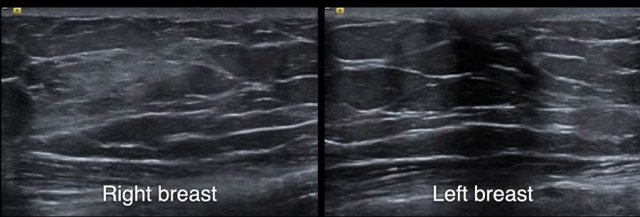

These images are of 70-year-old male who presented with a painfull swelling behind the right nipple.

Notice that there is some fibroglandular tissue on the right, while on the left there is only subcutaneous fat.